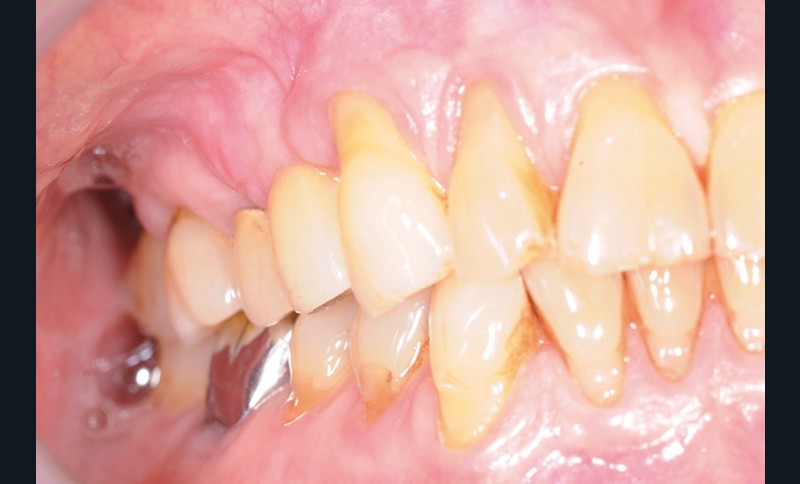

À la pose de la couronne implantaire, on notait une parfaite intégration des tissus mous(fig. 1a et b).

Lors de la maintenance de 2016, le contrôle de plaque de la patiente est toujours excellent et les tissus implantaires ne présentent pas de signes inflammatoires(fig. 2a et b).